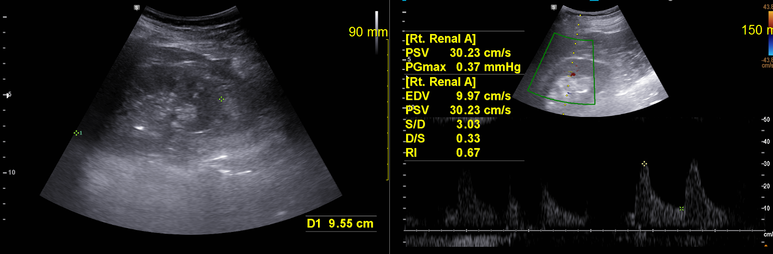

RI 정상범위임을 확인하였으나 양측 신장이 9-10cm로 크기가 약간 감소하여있다. 오래된 혈압에 의한 신장기능 저하를 확인할 필요가 있다.